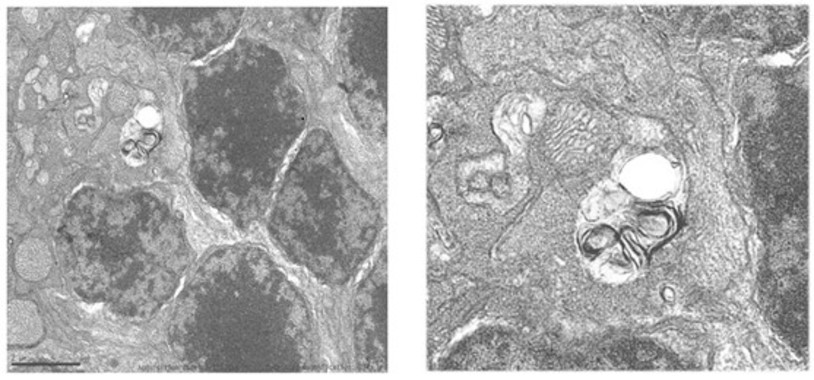

Diseñan una molécula que demuestra efectos protectores y regenerativos en el hígado graso